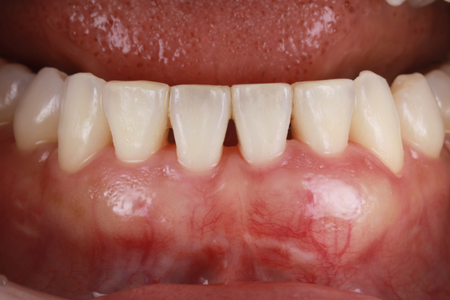

下がった歯茎を美しく、強く再生|

30代 男性

矯正治療と根面被覆術による口腔環境の改善

治療名 【審美・機能回復】歯肉退縮に対する根面被覆術+マウスピース矯正 治療期間 約1年 執刀医 Dr. 大杉 治療費 1,150,000円(税込)

■内訳:

矯正治療 900,000円

オペ費用 250,000円治療解説 歯肉退縮の改善と、将来的に歯を失うリスクを下げる目的で治療を行いました。

まずマウスピース矯正で歯列と噛み合わせを整えたうえで、結合組織移植による根面被覆を実施。

見た目だけでなく、歯を長く残すための安定性も重視して回復を図りました。リスク・副作用 歯の移動時に数日程度の違和感や疼痛が生じることがあります。

術後の過度なブラッシング圧や不適切な清掃用具の使用は、再度の歯肉退縮(再発)を招く主原因となるため、適切なケア指導の遵守が必要です。 -